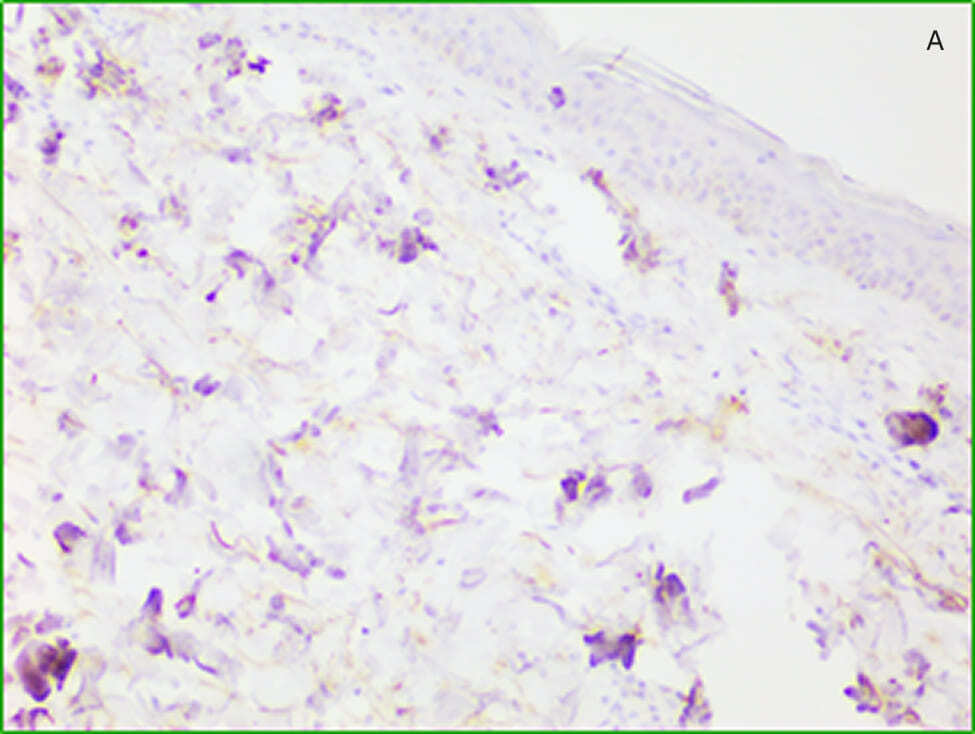

Рисунок 1. Результат гистологического анализа. А — образец до воздействия. Слабо выраженная лимфомакрофагальная инфильтрация, хаотично расположенные пучки коллагена. Б — образец после воздействия. Воспалительный инфильтрат отсутствует, коллаген нормального строения, слабо выраженный акантоз. Гематоксилин-эозин, увеличение х 10.

Иммуногистохимическая реакция на коллаген III типа в группе до лечения была слабоинтенсивной и рассеянной. После лечения интенсивность и площадь специфического окрашивания существенно увеличились, сигнал коррелировал с зонами реорганизации матрикса. Результат иммунотипирования коллагена III типа позволил установить, что большинство очагов неоколлагеногенеза приходится на периваскулярное пространство. Микрофотографии препаратов, подвергнутых иммуногистохимическому анализу, представлены на рисунке 2.

Рисунок 2. Результат иммунотипирования коллагена III. А — препарат до воздействия плазмой. слабо положительная реакция в мелких хаотично расположенных фокусах. Б — препарат после воздействия. Иммунореактивный продукт расположен вокруг капилляров и выводных протоков потовых желез. Стрептавидин-пероксидаза. Увеличение х 20.